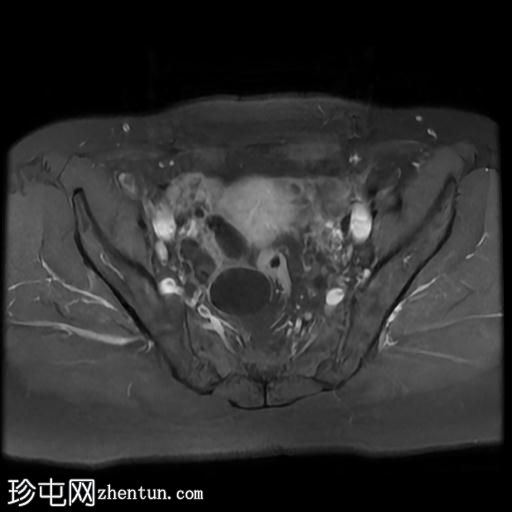

轴位

T1加权像

右侧输卵管呈管状囊性扩张,直径达30 mm,提示输卵管积水,呈均匀液体信号,无实性成分。

左侧输卵管亦有轻度扩张,直径26 mm,符合输卵管积水表现。

右侧卵巢可见一单纯性卵巢囊肿,大小约35 x 40 mm,呈正常液体等效信号。

宫内节育器位置正常。

MRI 检查结果显示双侧输卵管积水和右侧卵巢单纯性囊肿。总体而言,所有附件和盆腔检查结果均显示良性 MRI 特征(O-RADS 2 类),无恶性肿瘤迹象。